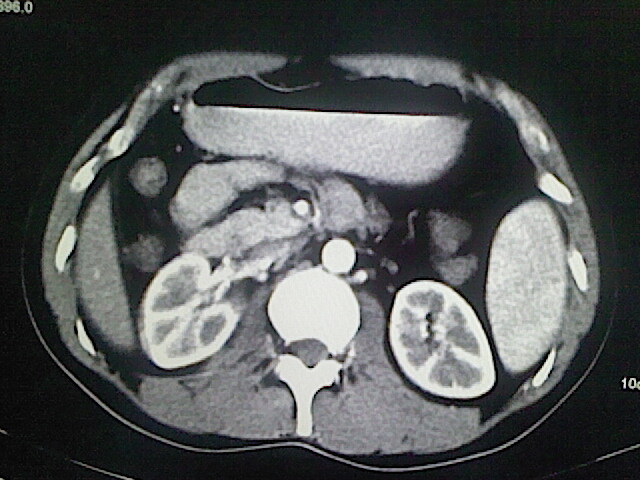

以下是引用卜一在2009-3-14 9:49:00的发言:[br]胆囊萎缩,胆囊壁不规则增厚,内部结构模糊,增强明显强化。另:肝左叶外侧段肝囊肿。支持:慢性胆囊炎!高度可疑:胆囊癌!

以下是引用余辉在2009-3-14 8:48:00的发言:[br]1)慢性胆囊炎。2)肝左叶外侧段肝囊肿。3)脂肪肝。[br]支持,胆囊萎缩,密度增高,不知b超具体有何提示,钙胆汁?结石?

以下是引用jiangjing在2009-3-14 10:18:00的发言:[br]1)慢性胆囊炎。2)肝左叶外侧段肝囊肿。3)脂肪肝。4.】建议行肝功能检查